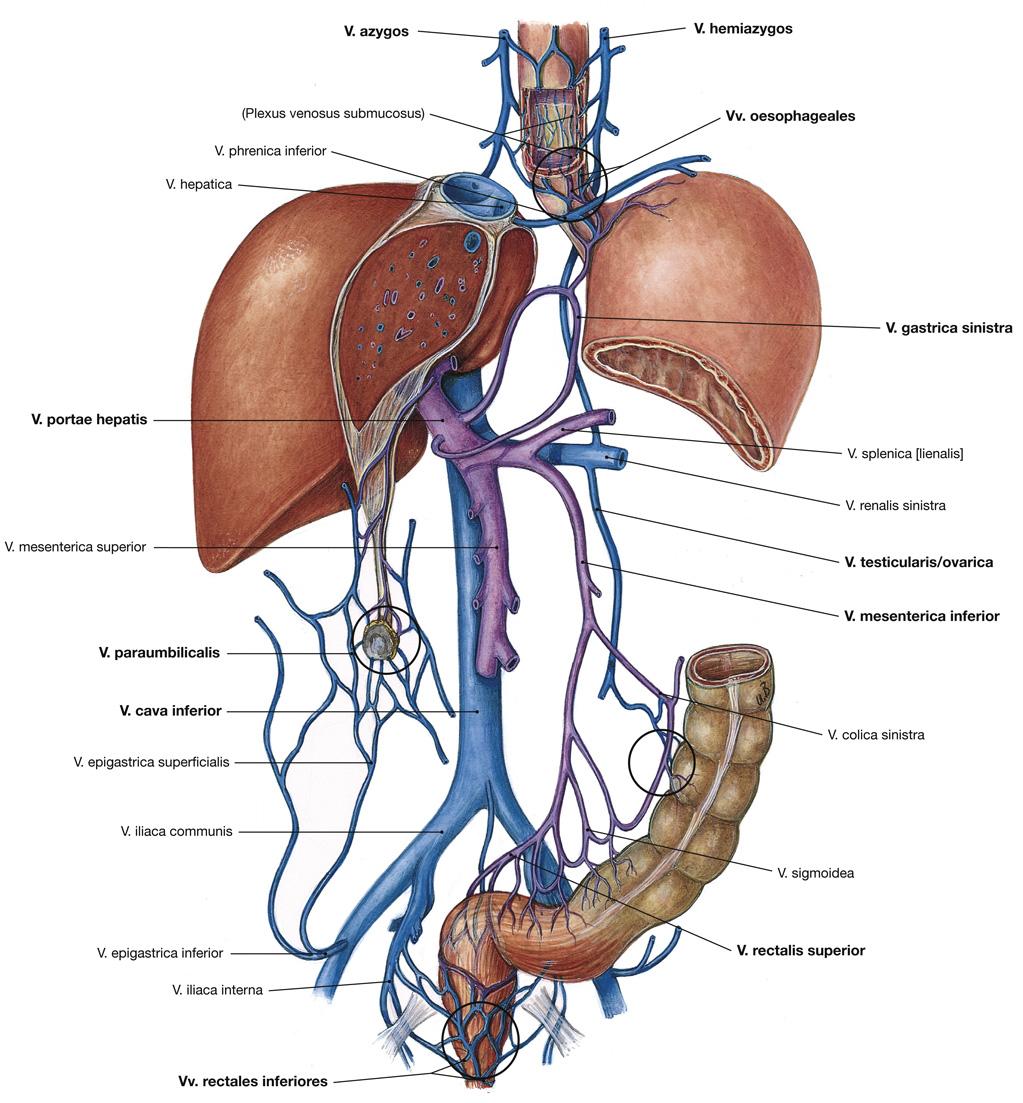

Fig 3.36: Vena portae hepatis

-

v portae

-

porto-cava shunt

bij blokkade v portae -

drie opties